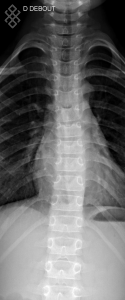

Radiographie du Rachis dorsal

Pour une radiographie du rachis dorsal, aucune préparation n'est requise. Il est recommandé d'enlever tous les bijoux avant de se présenter.

Vous serez installés en position debout.

La durée de l'examen est d'environ 5 minutes. Un ou plusieurs clichés radiographiques seront effectués. Le manipulateur vous positionnera en fonction de l'incidence radiologique à réaliser. Sauf indication contraire, il sera important de ne pas bouger durant la prise de clichés.

Avant de passer une radiographie du rachis dorsal, il est primordial de signaler si vous êtes ou pensez être enceinte. En effet, vous devrez passer l'examen sous certaines conditions.